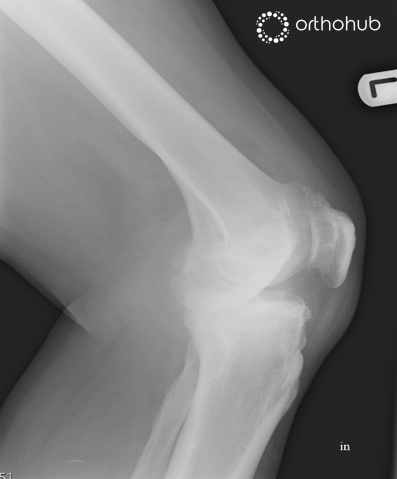

This is a 68 year old man has significant pain in his knee and has failed conservative treatment. He has no significant co-morbities.

On examination there is varus deformity with fixed flexion. Neurovascular examination is normal.